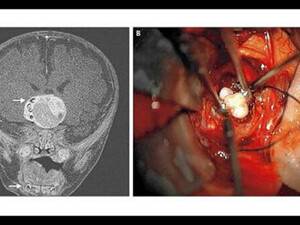

Bebeğin Beyninden Öyle Bir Şey Çıktı Ki!